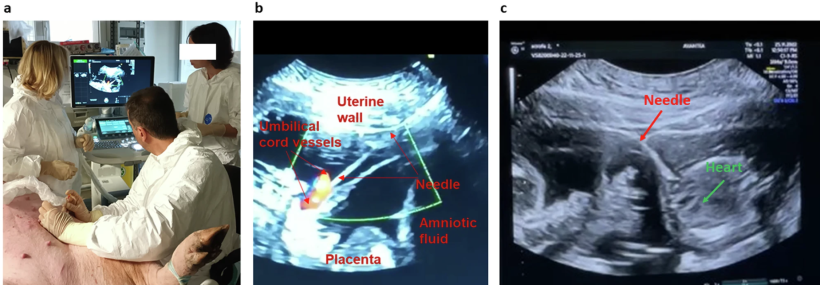

Materiali e Metodi: Abbiamo stabilito e validato un approccio mininvasivo, ecoguidato, per la somministrazione genica sistemica in feti di suini utilizzando un vettore AAV9 autocomplementare che codifica per GFP sotto un promotore CAG. Le iniezioni sono state eseguite a diverse età gestazionali (GA 80 e GA 108) per via intracardiaca o venosa ombelicale. Gli esiti postnatali sono stati monitorati e la biodistribuzione e l'espressione del transgene sono state valutate mediante qPCR, ddPCR, immunofluorescenza e Western blotting. La risposta infiammatoria, la tossicità e la sicurezza della scrofa sono state valutate attraverso il profilo citochinico e analisi istologiche.

Risultati: La procedura è stata ben tollerata, senza significativa morbilità della scrofa o esiti ostetrici avversi oltre un parto pretermine. L'analisi della biodistribuzione ha rivelato un'ampia presenza del vettore nei tessuti periferici, con una robusta espressione di GFP nel fegato e nel cuore. È importante sottolineare che non vi è stata alcuna evidenza di significativa tossicità tissutale, necrosi o fibrosi in nessuno degli organi analizzati. Sono stati osservati lievi aumenti delle citochine proinfiammatorie (GM-CSF, GRO-α, IFN-γ), ma non associati ad alterazioni istopatologiche. Non sono stati rilevati anticorpi anti-capside AAV9 nei sieri di suinetti o scrofe, suggerendo una minima risposta immunitaria al vettore. Questi risultati dimostrano la sicurezza, la fattibilità e l'efficacia dell'IUFGT ecoguidato nei suini, supportandone il potenziale come piattaforma traslazionale per il trasporto genico terapeutico nei feti affetti da gravi patologie congenite.